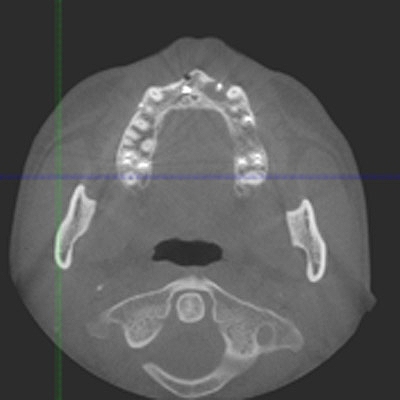

CTにより解剖学的形態を避け、安全に顎骨内にインプラントを埋入することが大切です。 CTが無いとインプラントはリスクが高いです

CTにより解剖学的形態を避け、安全に顎骨内にインプラントを埋入することが大切です。 CTが無いとインプラントはリスクが高いです

将来的に周囲の歯が無くなっても安定した位置への埋入

になっているかと思います

頬側が骨幅が取れるケースと取れないケースもあります